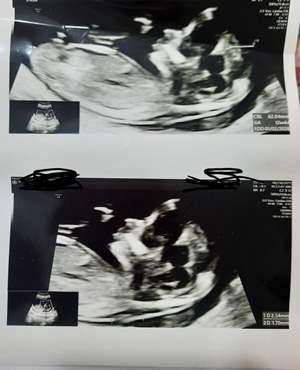

دیروز رفتم سونو دوازده هفته بچم شبیه خودمه حس میکنم